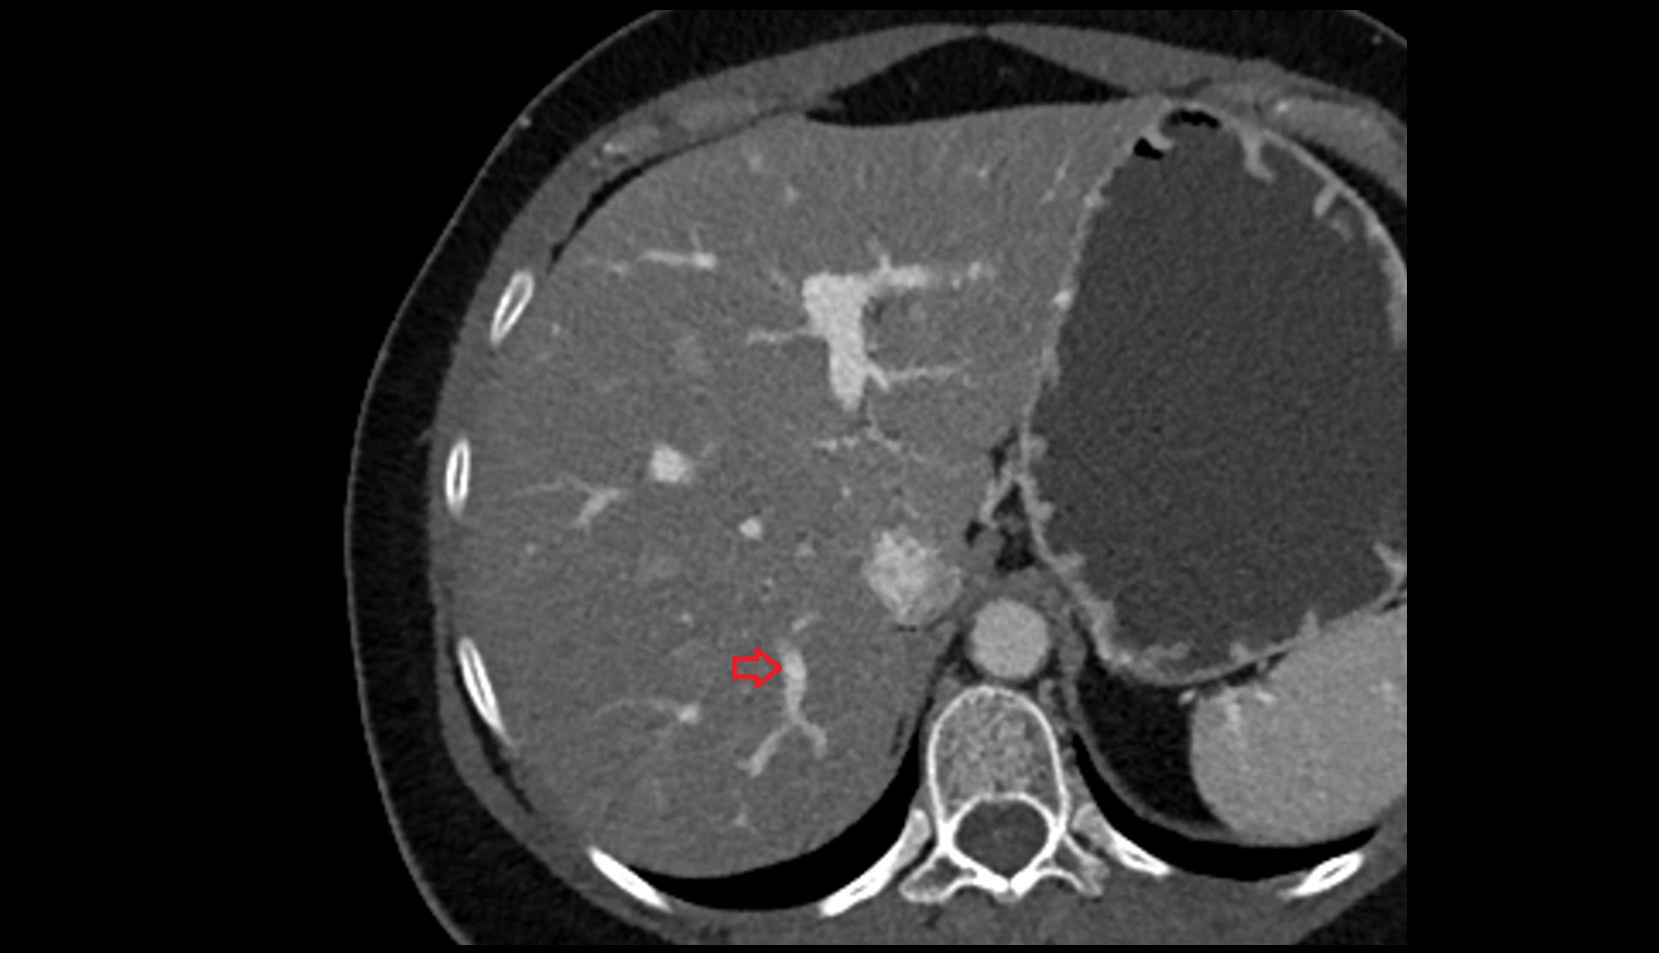

- Right lobe of liver

- Liver